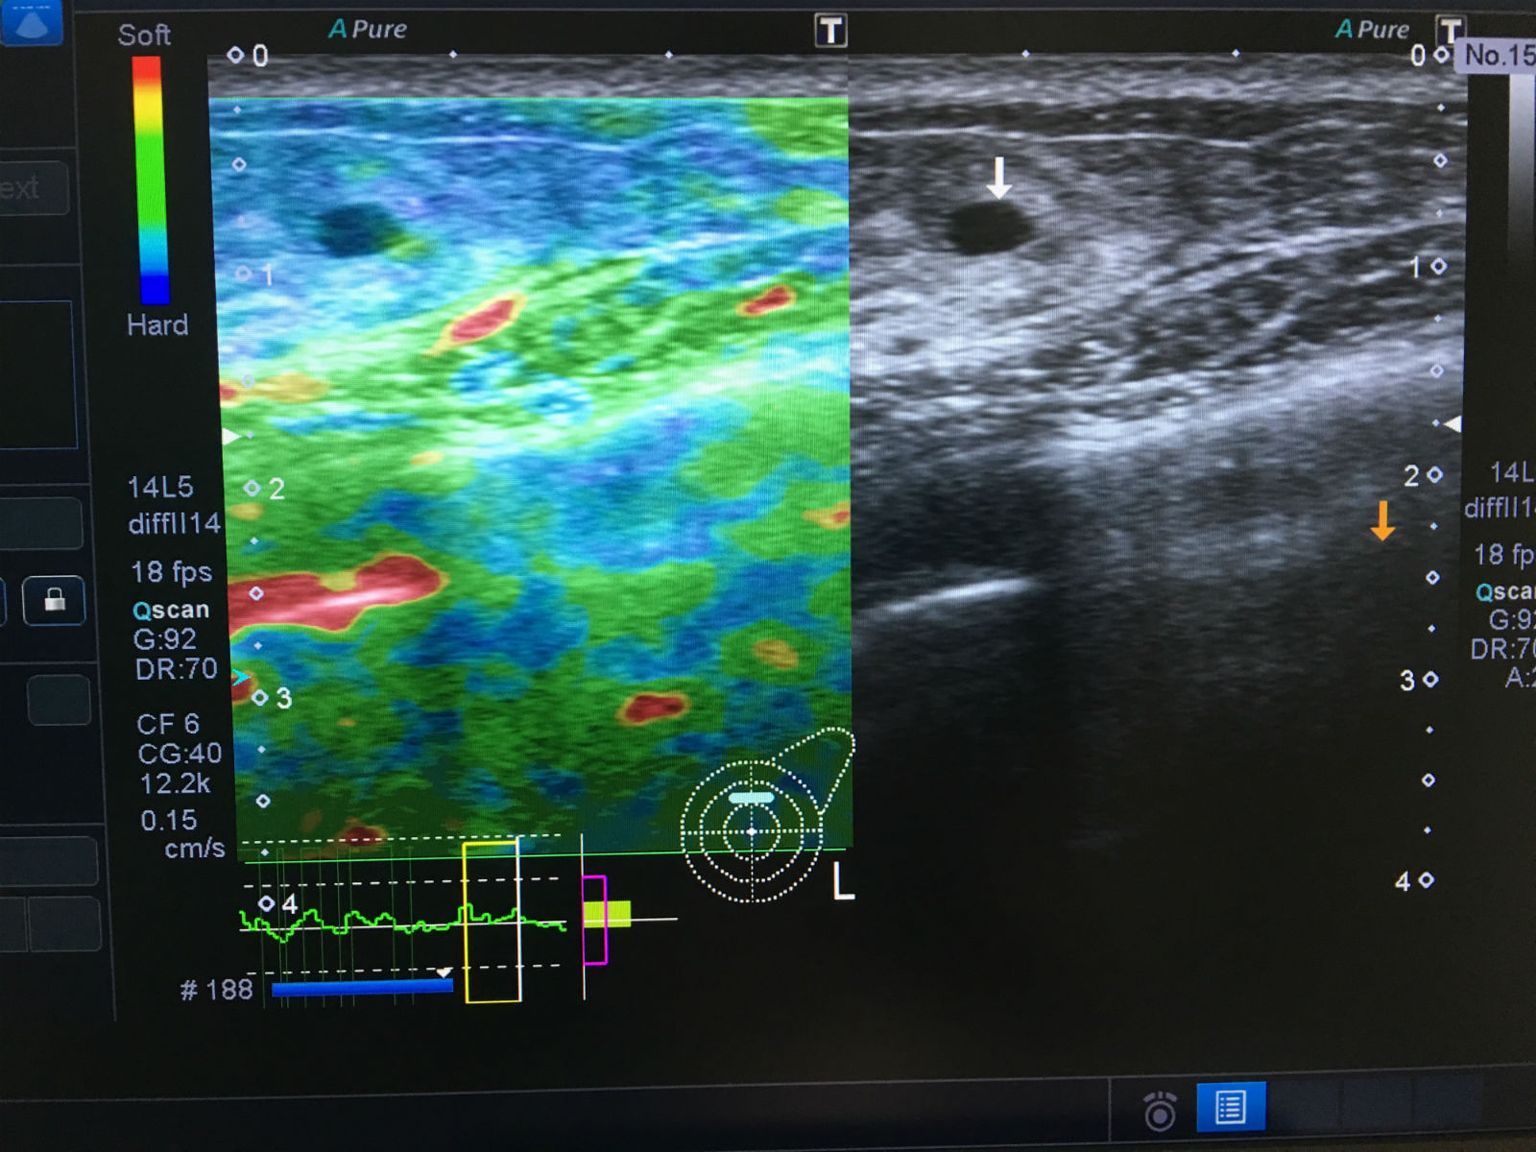

• Strain elastografija Foto: ultrazvuk-tarle.hr